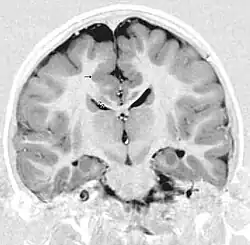

Gray matter heterotopia

Gray matter heterotopia is a neurological disorder caused by gray matter being located in an atypical location in the brain.[1]

Grey matter heterotopia is characterized as a type of focal cortical dysplasia. The neurons in heterotopia are otherwise healthy; nuclear studies have shown glucose metabolism equal to that of normally positioned gray matter.[2] The condition causes a variety of symptoms, but usually includes some degree of epilepsy or recurring seizures, and often affects the brain's ability to function.

Gray matter heterotopia are common malformations of cortical development known as neuronal migration disorders. Heterotopias are classed in two groups: nodular and diffuse. Nodular types are subependymal and subcortical; diffuse types are termed band heterotopias. Affected patients are generally divided into three groups, depending on the location of the formation: subependymal, subcortical, and band heterotopia. In addition, especially with heterotopia that are genetically linked, there are sex differences. Men seem to develop more severe symptoms than women with similar formations.

Periventricular means beside the ventricle, while subependymal (also spelled subepydymal) means beneath the ependyma; because the ependyma is the thin epithelial sheet lining the ventricles of the brain, these two terms are used to define heterotopia occurring directly next to a ventricle. This is by far the most common location for heterotopia. Patients with isolated subependymal heterotopia usually present with a seizure disorder in the second decade of life.

Subependymal heterotopia present in a wide array of variations. They can be a small single node or a large number of nodes, can exist on either or both sides of the brain at any point along the higher ventricle margins, can be small or large, single or multiple, and can form a small node or a large wavy or curved mass.